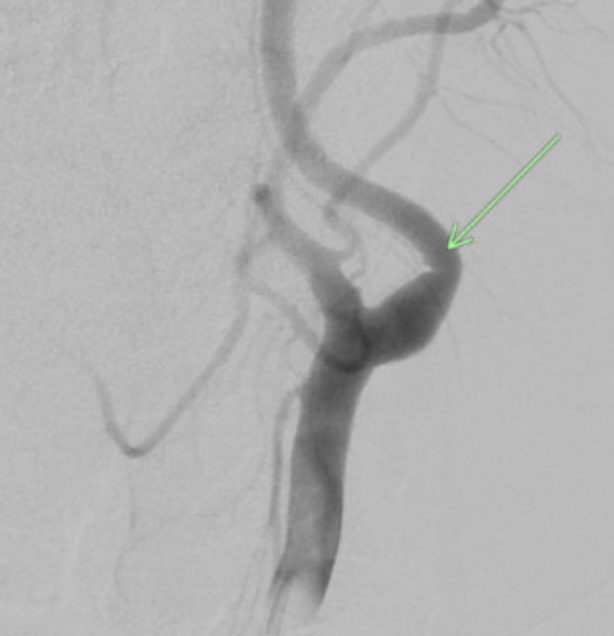

A 47-year-old woman with a history of well-controlled non-insulin-dependent diabetes mellitus and essential hypertension presented to the emergency department (ED) in 2015 complaining of right-sided facial, upper extremity, and lower extremity weakness with associated dysarthria. The patient was in her usual state of health until 1 hour before presentation. A computed tomography (CT) scan revealed ischemic stroke on the left side of the basal ganglia and posterior limb of the internal capsule. Magnetic resonance imaging (MRI) showed an acute infarction of the left motor cortex. The patient was given tissue plasminogen activator (tPA) and admitted. During admission, cardiac telemetry and transthoracic echocardiography were unrevealing. She was discharged on 81 mg of aspirin and 40 mg of atorvastatin 40 mg with cardiology follow-up. A loop recorder was implanted for 4 weeks and did not show evidence of atrial fibrillation. After 14 months, the patient returned complaining of 30 minutes of similar symptoms. MRI revealed an acute ischemic infarct in the left frontal corona radiata with chronic microvascular ischemic changes. The patient received tPA and fully recovered after 3 days of hospitalization. Telemetry was negative for atrial fibrillation and transesophageal echocardiography showed no evidence of left atrial appendage thrombus or patent foramen ovale. A digital subtraction angiography (DSA) was performed, which confirmed the presence of a small intimal web on the proximal cervical left internal carotid artery (Figure 1), but there was no evidence of significant cerebral stenosis or vasculitis.

Recurrence of cardiovascular accidents (CVA) occurs frequently. Studies have demonstrated recurrence of CVA in 26% of patients within 5 years.3 This case reports a patient on antiplatelet therapy with recurrent CVA with no identifiable cause. Her stroke was classified as cryptogenic due to a lack of evidence of etiology despite repeated tests to rule out cardioembolic, aortoembolic, or atheroembolic causes. Since all the strokes occurred within the region of the left internal carotid artery (Figures 2-4), we suspect they were caused by the left internal carotid web. During DSA, the neurosurgeon noted in the operative note that the extracranial left carotid artery circulation exhibited normal caliber and course, with the exception of a very small, eccentric intimal web at the junction of the left internal carotid artery bulb and proximal cervical segment. While most carotid webs are found in the carotid bulb’s posterior margin, the carotid web in this case appeared in the anterior and distal aspect. Theoretically, a carotid web could form anywhere along the carotid artery where a thin, membrane-like shelf of tissue that extends from the wall to the lumen exists. The multitude of infarcts in the left internal carotid’s territory helps to support that this patient has a carotid web rather than a kinked or tortuous vessel, and that it has a probable role in stroke etiology.